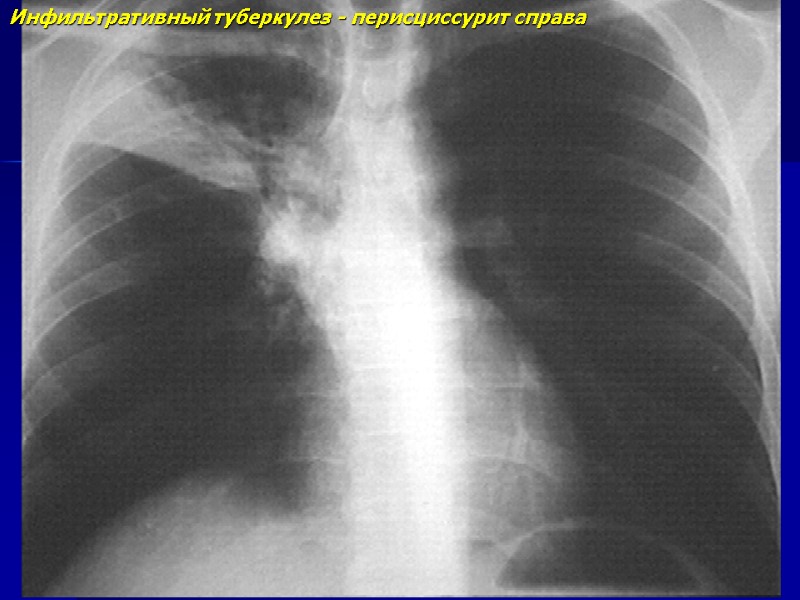

Инфильтративный туберкулез - перисциссурит справа